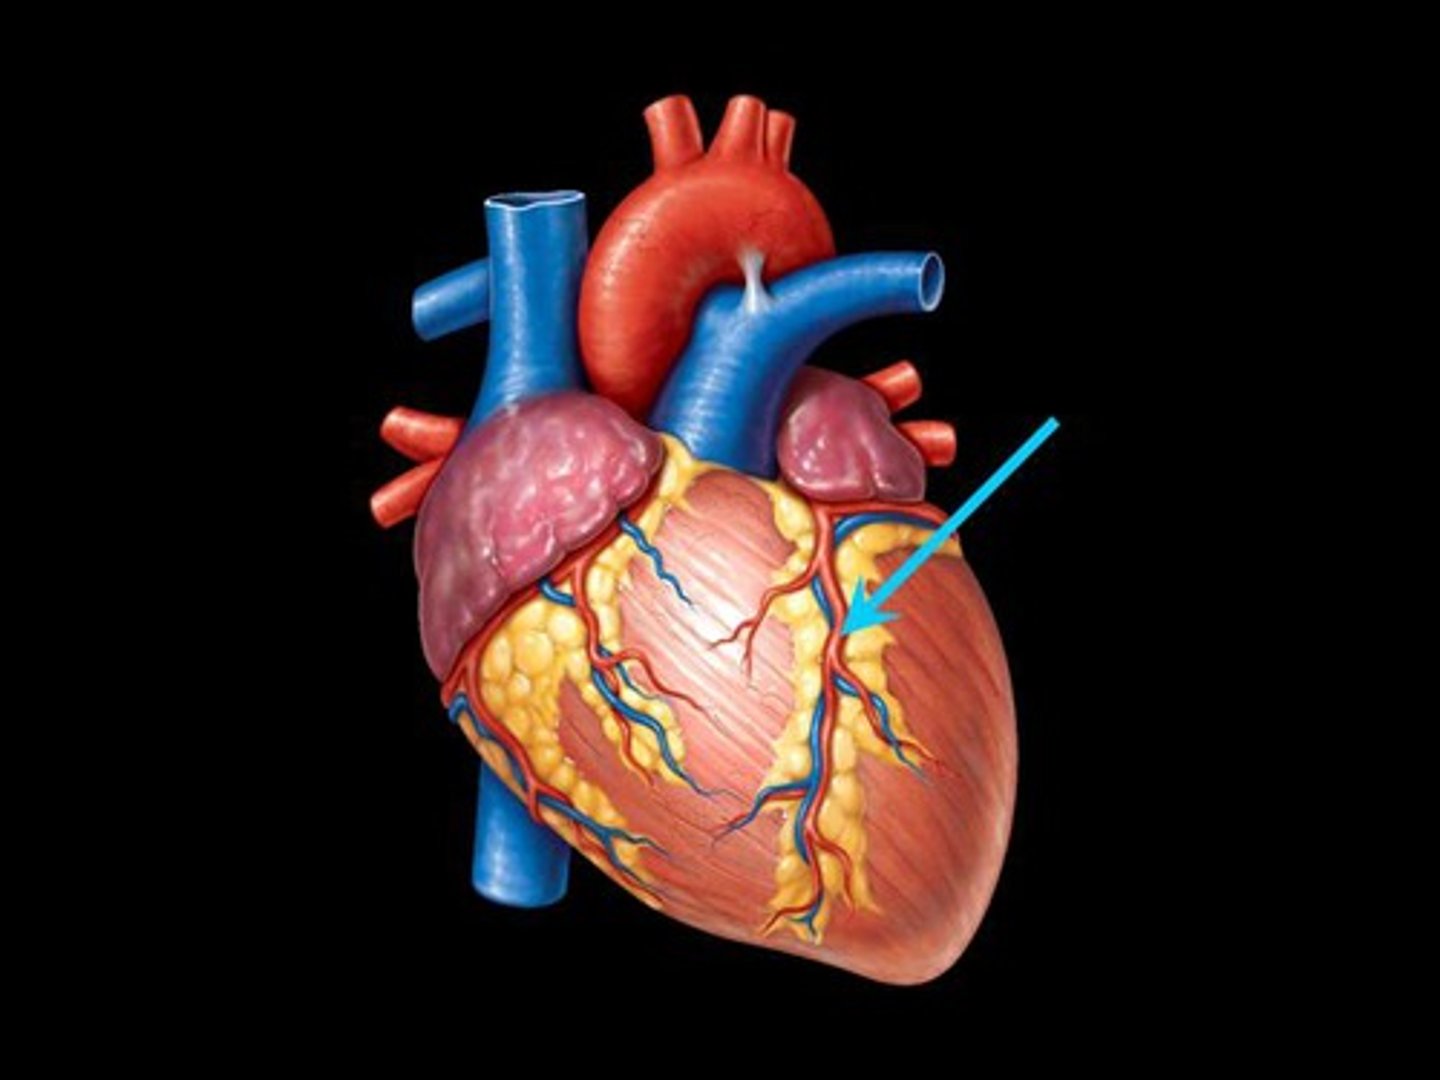

anterior interventricular sulcus

Depression; divot on right side, anterior, by right ventricle

H1

anterior interventricular artery

Structure; sits in anterior sulcus, anterior side, curly tube

17

Circumflex artery

st

on left border of heart, curly

comes off L coronary arter

18